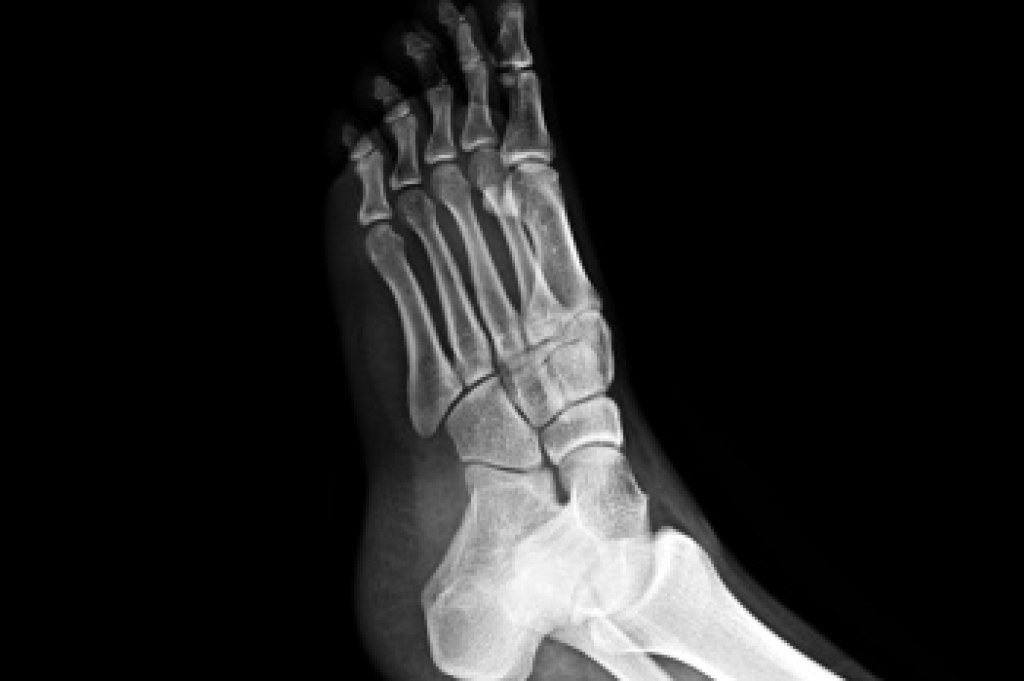

To figure out the cause of foot pain, podiatrists utilize several different methods. This can range from simple visual inspections and sensation tests to X-rays and MRI scans. Prior medical history, family medical history, and any recent physical traumatic events will all be taken into consideration for a proper diagnosis.